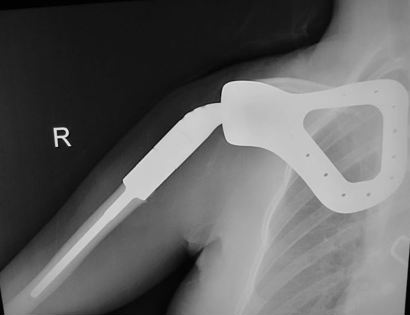

This image shows the total scapula prosthetic replacement as seen on an X-ray.

This is a second-generation scapular prosthesis. This allows the muscles a better area to attach in order to give the shoulder more stability.

The scapula prosthesis is placed with the upper part of the humerus prosthesis already seated in place. The humerus portion of the prothesis is cemented and then the scapula prosthesis is sutured to the chest wall. This allows for proper positioning and function of the arm.